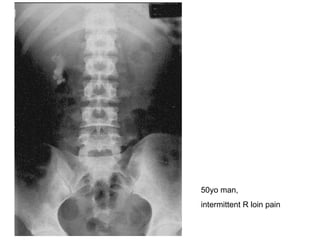

50yo man,  intermittent R loin pain

AXR/KUB- renal calculi Describe? Radio-opaque mass noted at R kidney Dx? Renal staghorn calculi Cx? Hydronephrosis/pyelo-nephrosis/-nephritis Renal failure SCC 2 other Ix? IVU (filling defect/impaired renal fx) Renal U/S (exclude hydronephrosis/hydroureter)

AXR/KUB- renal calculiDescribe? Radio-opaque mass noted at R kidney Dx? Renal staghorn calculi Cx? Hydronephrosis/pyelo-nephrosis/-nephritis Renal failure SCC 2 other Ix? IVU (filling defect/impaired renal fx) Renal U/S (exclude hydronephrosis/hydroureter)